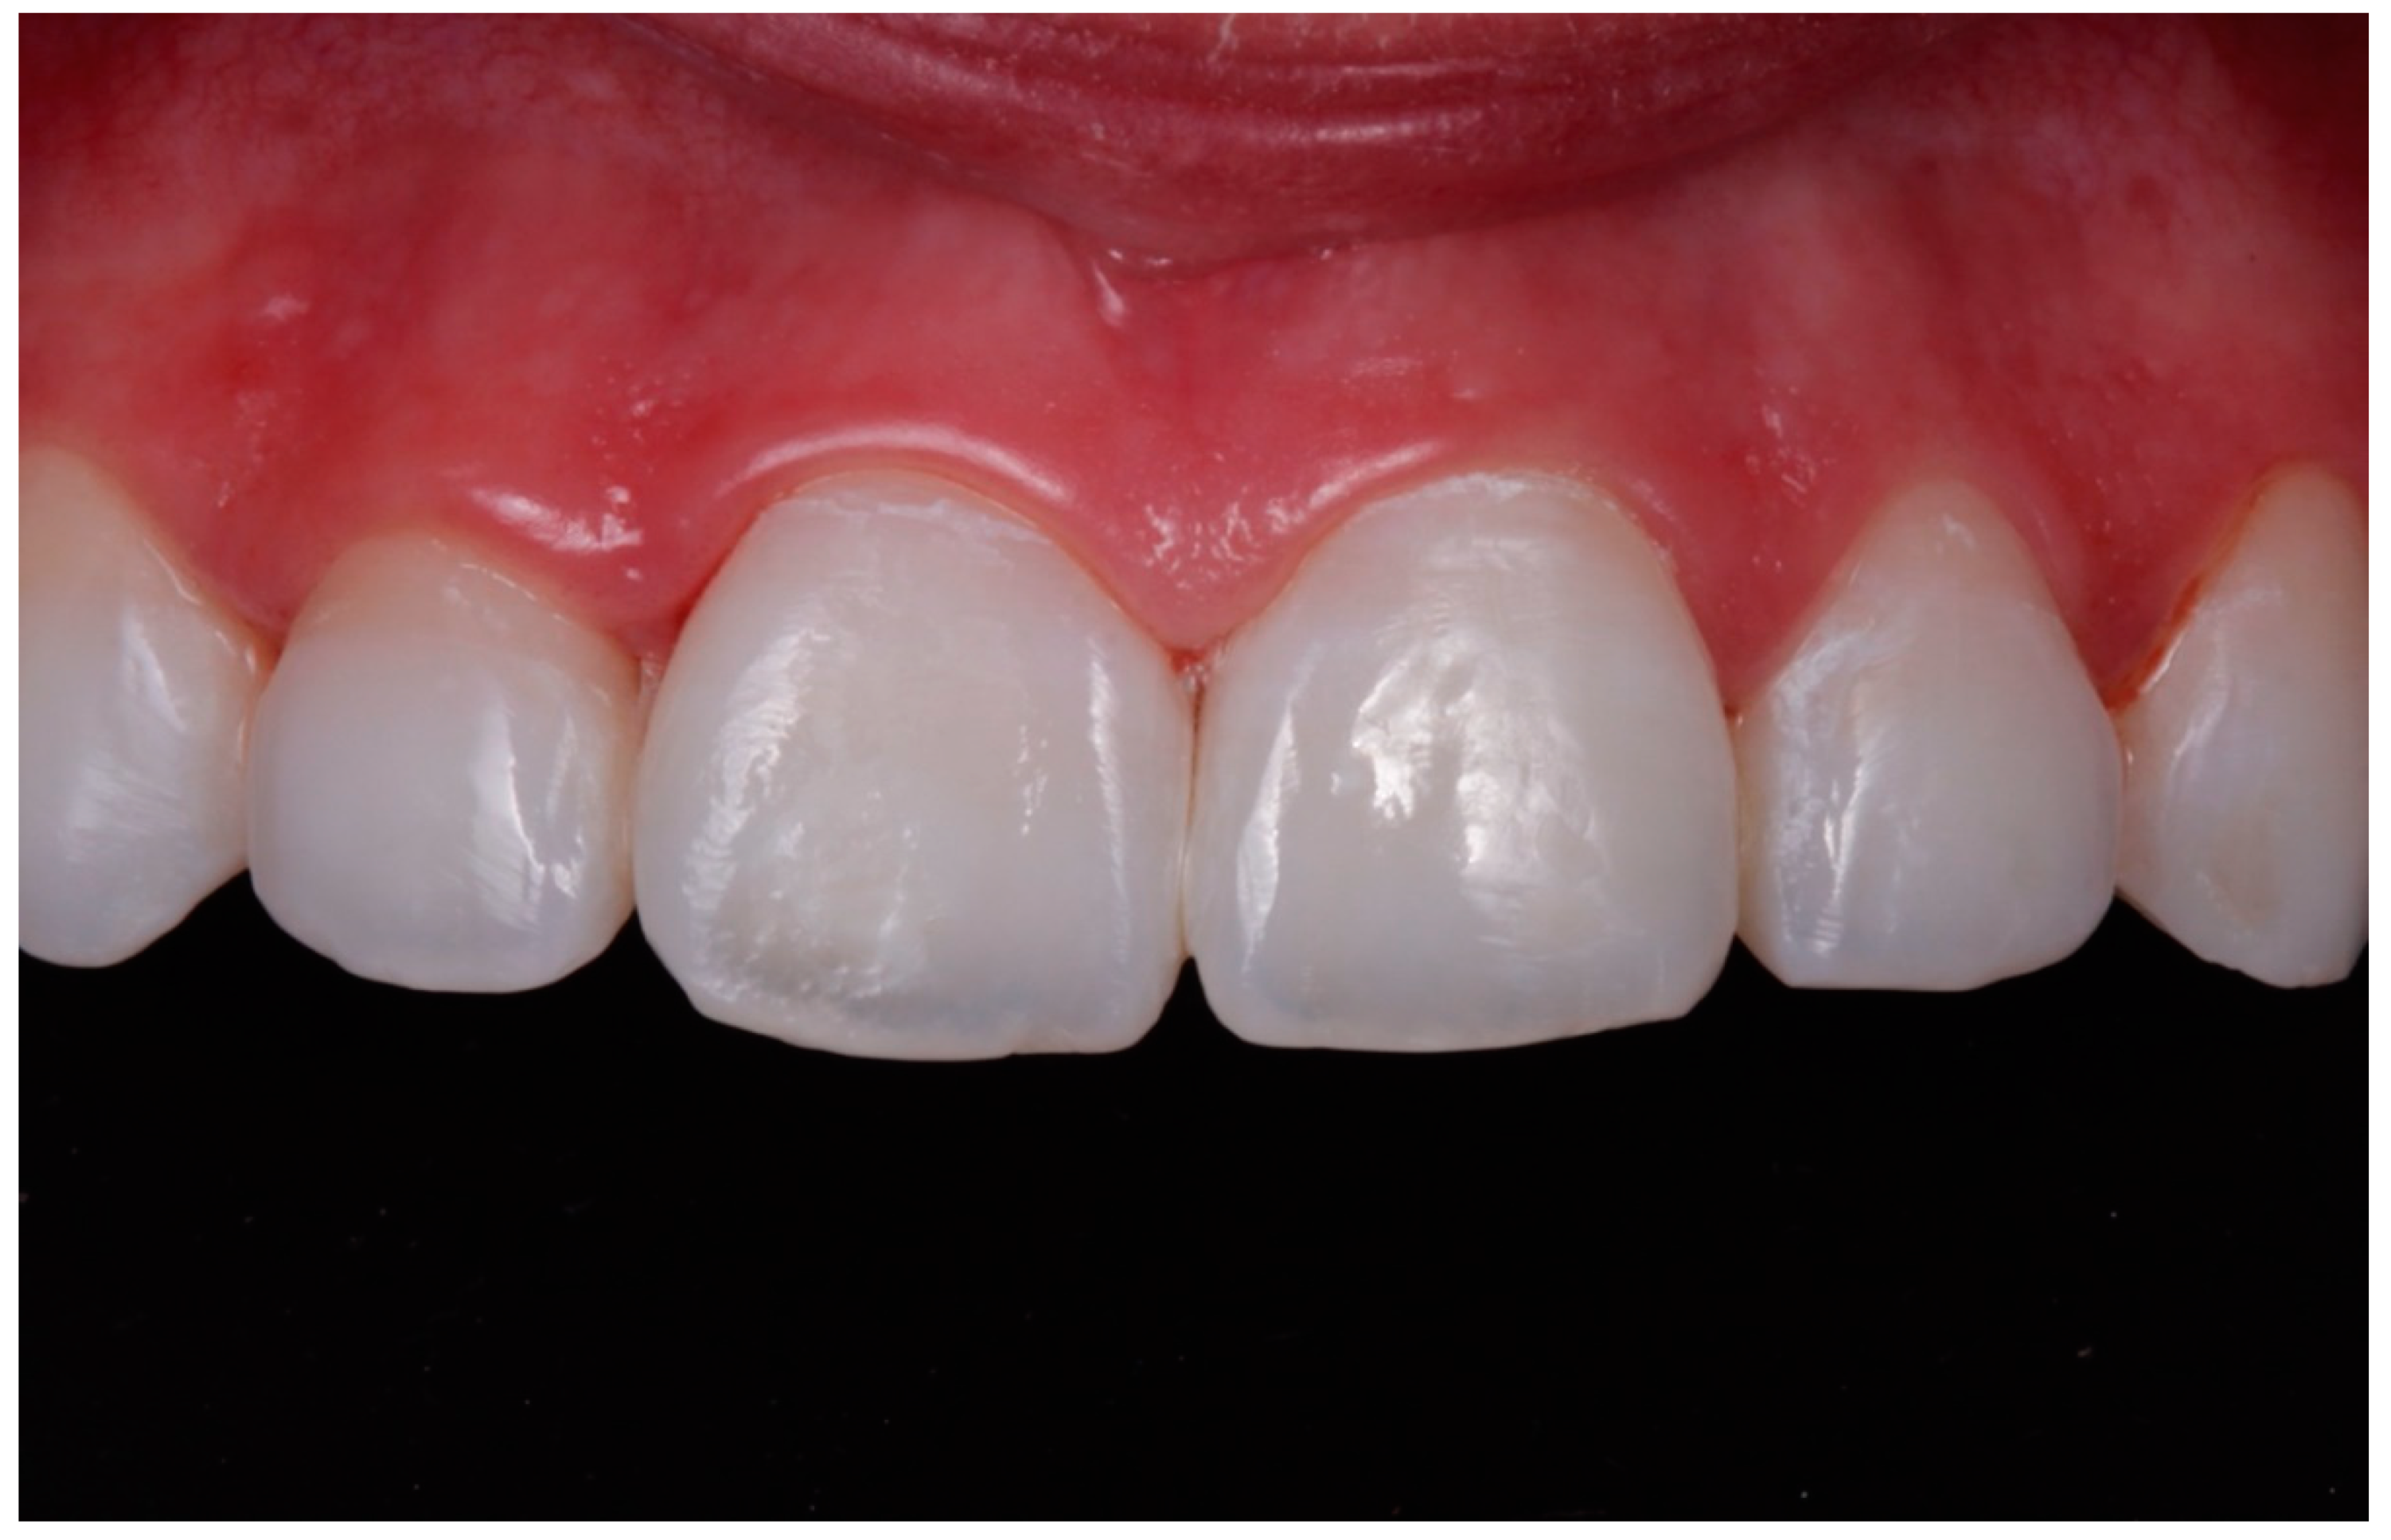

- In cases where the 15% HCl product was applied (ICON etch; DMG), each affected tooth received three applications of chemical erosion treatment for two minutes each. The product was placed with the tip of a sponge applicator on the enamel surface for 2 min. When 2 min had passed, the enamel was washed with abundant water for 30 s (Figure 1, Figure 2 and Figure 3).